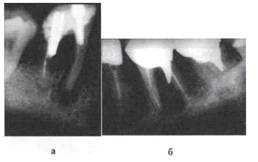

Рис. 6-2. Изгиб инструмента в корневом канале при

недостаточном вскрытии полости зуба. Рентгенограмма

Прежде чем создать доступ к полости зуба, необходимо сделать

рентгеновский снимок, который даст информацию о положении зуба в челюсти,

наклоне коронки зуба к корню, наклоне зуба, количестве каналов в корнях, их

проходимости, выраженности деструктивных изменений в периодонте.